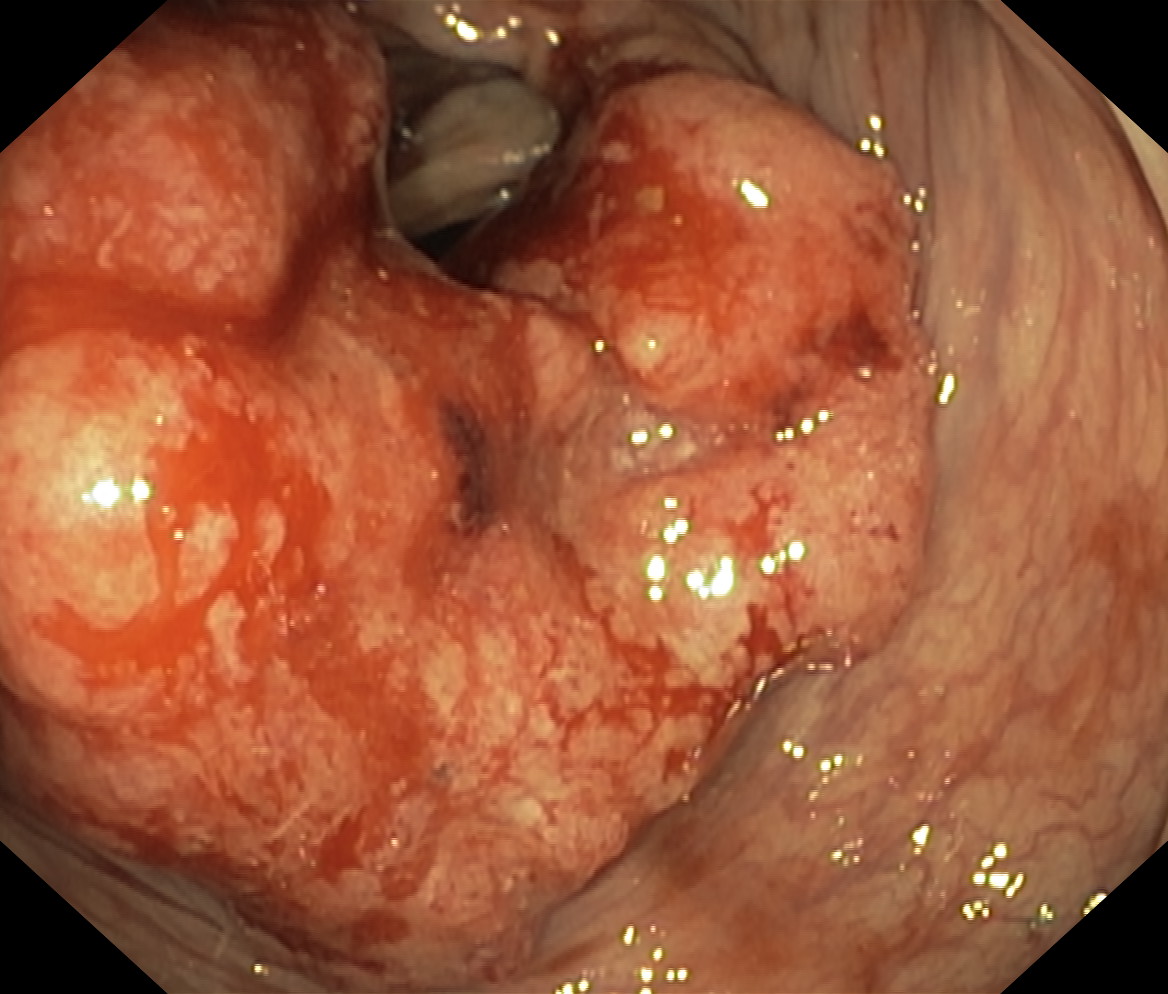

Nowotwory przewodu pokarmowego